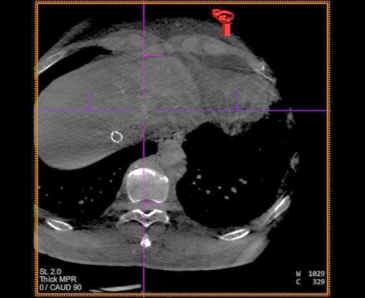

患者仰卧,右侧腹股沟区消毒铺巾,穿刺右股动脉,置入5.0Fr 导管鞘,经鞘进入 RH 导 管,在主动脉弓处成形,选择性进入腹腔干,行血管造影,肝右叶无明显肿瘤染色,肝左动 脉由胃左动脉发出,采用科睿驰医疗提供“智鹏”2.0Fr 微导管选择进入肝左动脉造影,行CBCT 扫描可见肝左内叶肿瘤强化病灶,大小约 1cm,肝左外叶病灶与胃左动脉分支共干,无法避开进一步超选择,超选择进入肝左内叶,造影明确到达把血管,选用 100-300μm“睿 渊”DiaSphere®载药微球加载 50mg 表柔比星,载药完毕后,予注入 2ml 载药微球,再 次行 CBCT 扫描,原肝左内叶病灶无强化,术中患者生命体征平稳,撤出导管,压迫止血、 包扎,患者安返病房。

术中 CBCT 可见肝左内叶肿瘤强化病灶

CBCT 扫描血管重建可见,血管迂曲及靶病灶大小和位置

栓塞结束后 CBCT 扫描,原肝左内叶病灶无强化